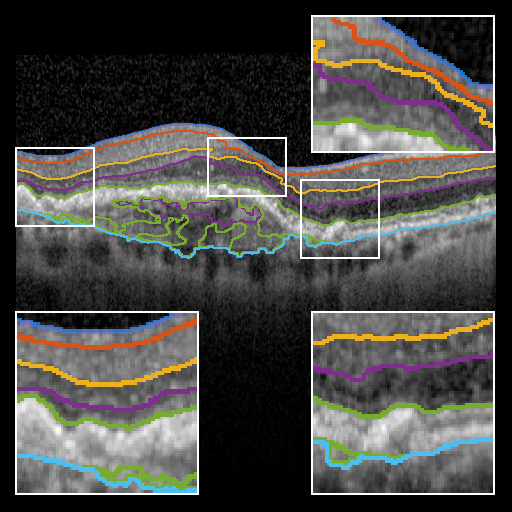

To evaluate BRU-net, we compare it with the 3D methods of Dufour [5], Chen et. al. [4], and the 2D method of Mayer et. al. [12] on the same dataset. Additionally, we train a traditional U-net configuration [14] using the procedure described above. Fig. 3 provides a qualitative comparison of the results.

To quantify those results, we make use of two metrics: (1) the Chamfer distance [2] between each ground truth layer boundary and the boundary produced by a given method and (2) the Dice score of each predicted layer surface. Note that BRU-net is not constrained to convex shapes. Since pathological retinal layers may be non-convex, other metrics that rely on pixel distances are ill-suited for this problem. Fig. 4 demonstrates the performance of each of the evaluated methods.